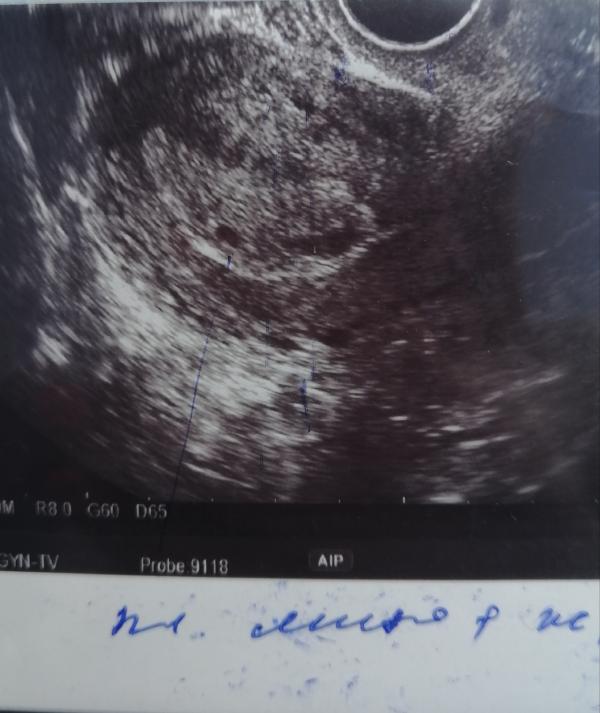

*Фото узи неделю назад

Но сроку соответствует )) 6-7 недель

Поздравляю! Сколько плодное яйцо у вас?